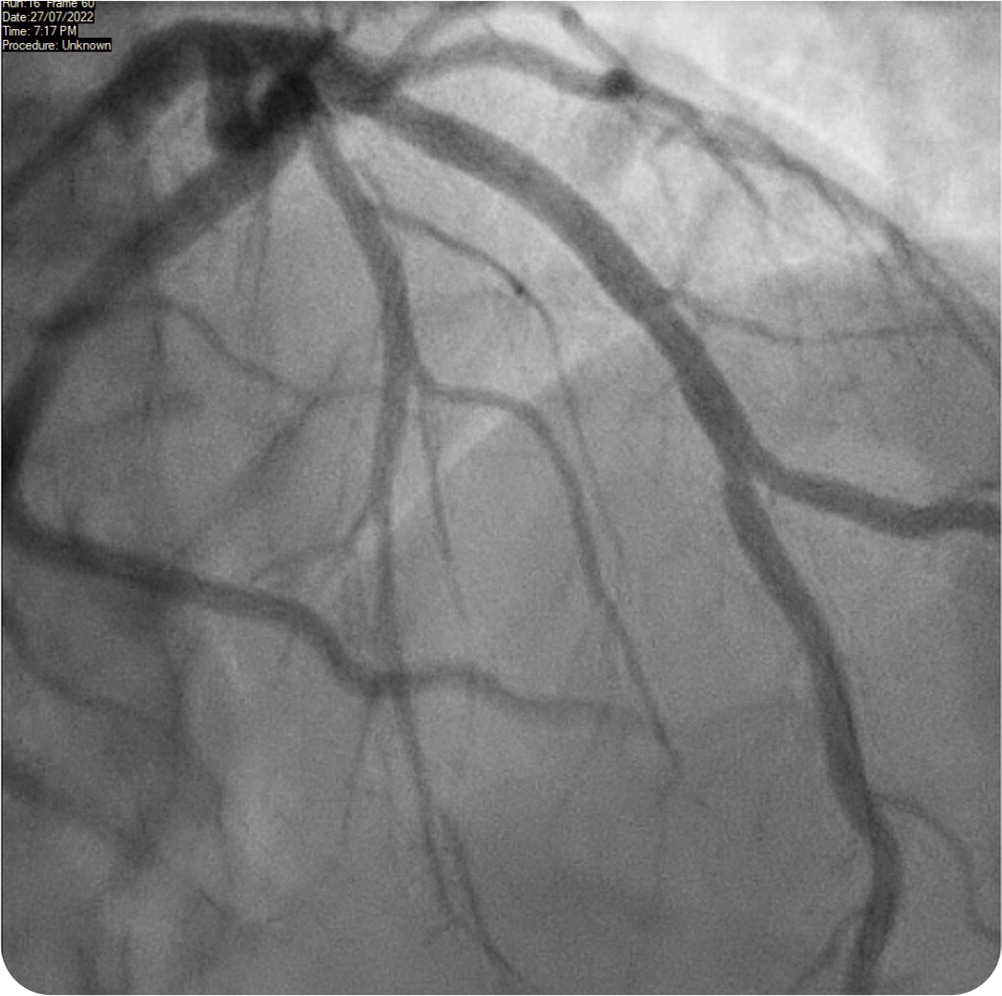

The answer is E: Wellens syndrome, defined by deeply inverted or biphasic T waves in leads V2 and V3 that are highly specific for critical stenosis of the left anterior descending coronary artery 2 (Figure 2). This patient had the typical presentation of Wellens syndrome, with episodes of intermittent chest pain caused by sudden occlusion of a previously stenotic coronary artery.3 These episodes are not usually captured by electrocardiography. Reperfusion of the left anterior descending coronary artery by spontaneous clot lysis resolves the chest pain but causes T waves to become biphasic in the corresponding V2 and V3 leads.4

These episodes also feature an isoelectric or minimally elevated ST segment (less than 1 mm), preserved precordial R-wave progression, and a lack of precordial Q waves. Patients have normal or minimally elevated serum troponin levels. This patient was transferred to the emergency department, where repeated electrocardiography showed persistent T-wave changes. Initial troponin levels were normal (34 ng per L [34 mcg per L]), with subsequent measurement showing mild elevation (95 ng per L [95 mcg per L]). Twelve hours later, he underwent percutaneous coronary angioplasty, which revealed 95% stenosis of the proximal left anterior descending coronary artery (Figure 2). The patient was treated with a drug-eluting stent (Figure 3), and subsequent echocardiography showed preserved ejection fraction.